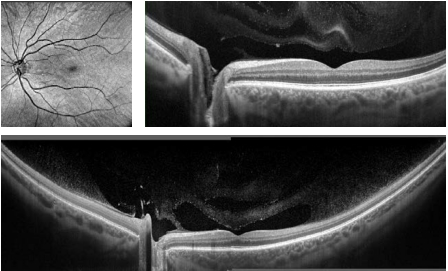

Является безопасной технологией без применения красителя, с ее помощью можно сделать видимым микроциркуляторное русло сетчатки глаза. Течение крови и полноценная визуализация предоставляют важные недостающие сведения для обнаружения болезней сетчатки. Сканированные изображения ангиографии помогают исследованиям сосудистой сети макулы, периферии и оптического диска. Эта процедура производится за очень маленький промежуток времени – 1,6 секунды при разрешающей способности "стандарт" или приблизительно 3 секунды при разрешающей способности "высокая".

Cетчатка

Одно отсканированное изображение макулы в 3D позволяет провести диагностику сетчатки и глаукомы. ПО в автоматическом режиме различает 8 слоев сетчатки, это необходимо для качественного исследования и формирования диаграммы изменений в здоровье больного человека. Наличие совершенно разных методик обработки результатов и презентации дает возможность отдать предпочтение наиболее действенной для пациента, увеличивая эффективность работы.